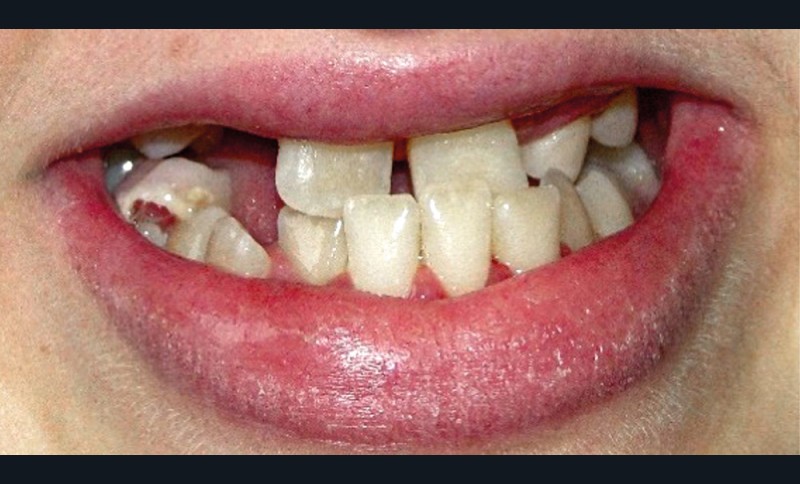

Au niveau exo-buccal, une classe III squelettique par brachymaxillie séquellaire est observée. L’hypodéveloppement de l’étage moyen de la face est l’une des conséquences de la radiothérapie reçue par la patiente dans sa jeunesse (fig. 2a à d) [4].

Au niveau endo-buccal, une mobilité des dents maxillaires, en particulier des incisives centrales (11 et 21), est remarquée. Elle peut s’expliquer par les séquelles dentaires du traitement par radio-chimiothérapie, bien visibles sur la radiographie panoramique (fig. 3). Au maxillaire…